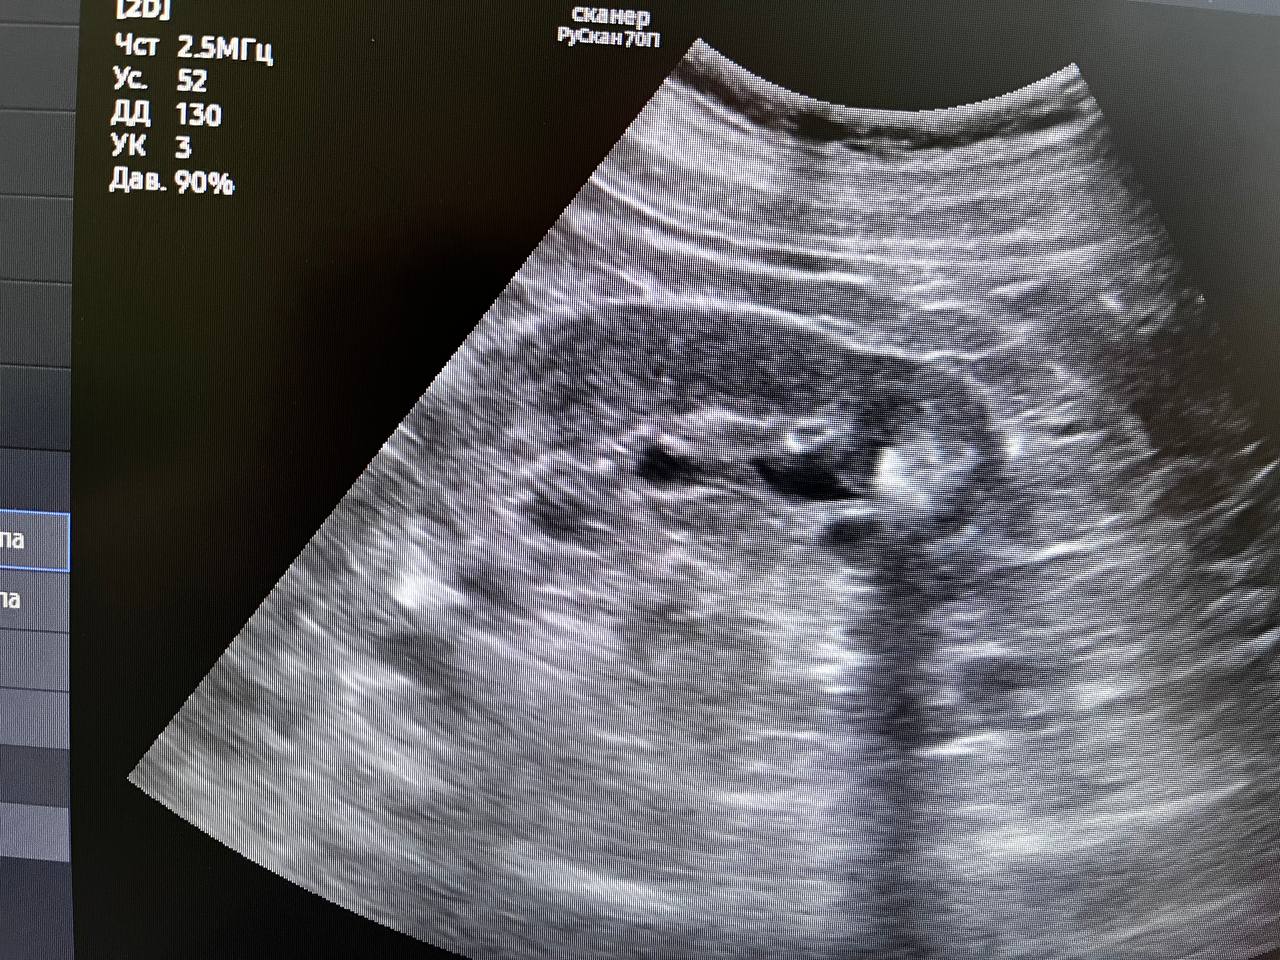

В минувшую субботу в день здоровой почки проверить своё здоровье пришли 22 человека. У двоих из них выявлены серьёзные патологии при полном отсутствии жалоб. Остальные пациенты были с мелкими кистами почек до 10мм и "песочком". Всем выполнено УЗИ, выданы направления на лабораторные обследования. Так же были пациенты без патологии, пришедшие для комплексного обследования со стороны мочевыделительной системы, выполнено УЗИ, выданы направления на общий анализ мочи

"У одного пациента - мочекаменная болезнь, чашечные камни с обеих сторон до 15мм. Направлен на МСКТ для установления точной локализации и положения камней с целью подготовки для плановой госпитализации и оперативного лечения. У второго пациента выявлено образование в правой почке до 12мм. Пациент направлен на МСКТ для верификации",

- уточнил врач-уролог поликлиники для взрослых обособленного подразделения им. М.В. Гольца Щёлковской больницы в г. Фрязино Владимир Орленко